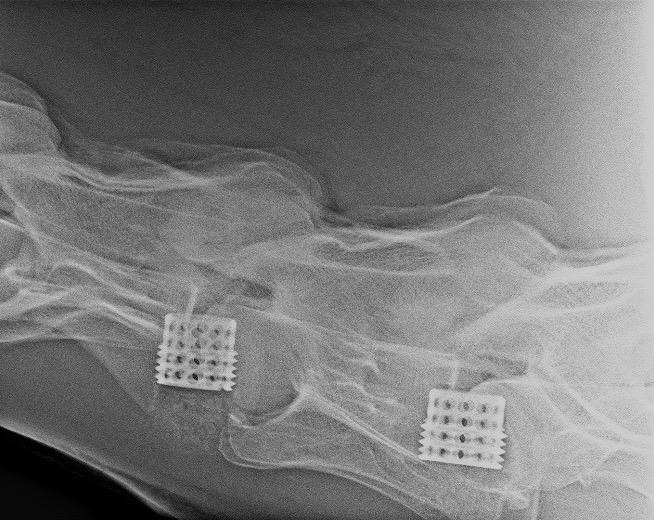

Artrodéza se provádí s použitím titanového implantátu, který je celosvětově známý jako Seattle Slewův košík (obr. 8, 9 a 14).

Obrázek 14: Protéza sloužící k chirurgickému zákroku, známá jako Seattle Slewův košík

Známý dostihový kůň jménem Seattle Slew začal trpět závažnou ataxií. Dr. Grant ho operoval s použitím vylepšené protézy a kůň poté prožil ještě velmi úspěšnou dostihovou kariéru. Kůň je při artrodéze operován v celkové anestezii a je položený na zádech (obr. 10–13).

Relativně malý, asi patnácticentimetrový řez se provádí ve spodní části krku (obr. 10) v úrovni problematického místa. Průdušnice a svaly jsou odtaženy stranou a přístup ke krčním obratlům je uvolněn (obr. 11). Titanová protéza je umístěna pod rentgenologickou kontrolou tak, aby dokonale stabilizovala oba obratle (obr. 12). Pokud se vyskytuje více míst, kde dochází ke zvýšení tlaku na míchu, je možné spojit i více obratlů (obr. 9). Tento chirurgický zákrok je v Equitomu zcela běžný a zabere přibližně jeden a půl hodiny (obr. 13).